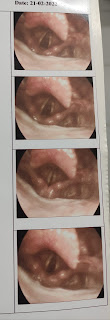

Direct laryngoscopy

( done in other hospital before admission)